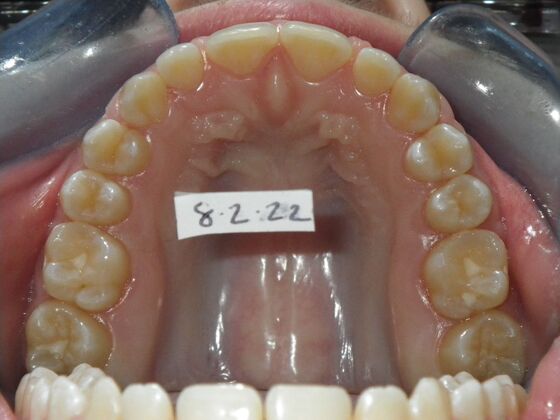

Patient presents desiring all spaces on upper and lower teeth closed. She will need slight expansion of upper arch due to lower molars leaning inward toward tongue. Used nitanium palatal expander with built in rotation of upper molars and lower lip bumper to upright lower first molars. Patient was also informed that her upper lateral incisors would require bonding due to their small size to close all space.